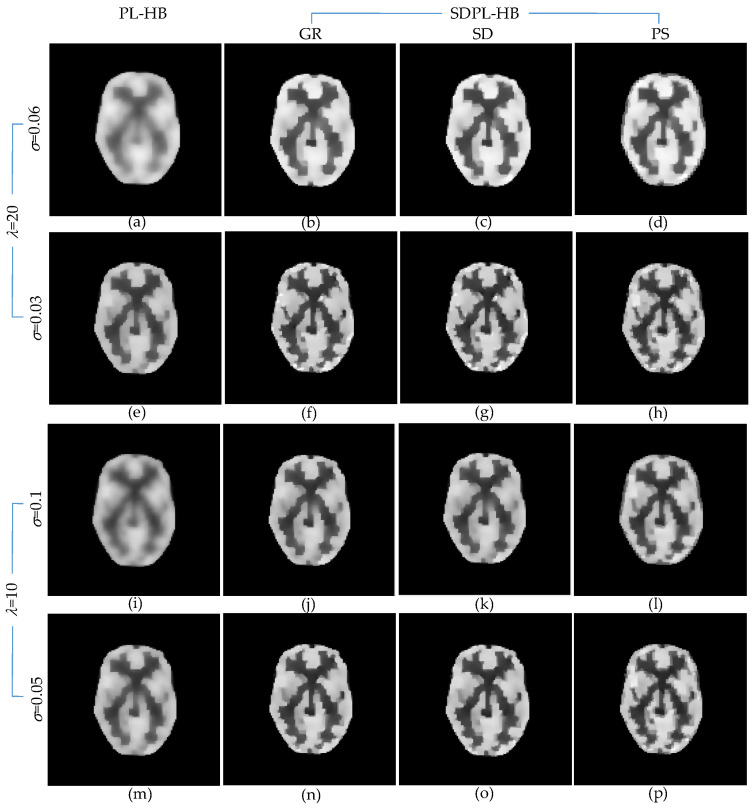

Figure 8 presents the anecdotal reconstructions using the HB penalty function, following the same layout as Figure 6 for the LN penalty function. Similar to the findings in Figure 6, the SDPL reconstructions consistently exhibit superior preservation of details compared to the standard PL reconstructions across all hyperparameter settings.

Figure 8.

Anecdotal reconstructions using PL-HB and SDPL-HB with two different (high and low) levels of λ and two different (high and low) levels of σ for each λ. (The results in the first column (a,e,i,m) are PL-HB reconstructions, whereas the rest of the results are SDPL-HB reconstructions). (a–h) λ =20 (i–p) λ =10 (a–d) σ = 0.06; (e–h) σ = 0.03; (i–l) σ = 0.1; (m–p) σ = 0.05.

Table 2 presents a performance comparison between the PL-HB and SDPL-HB methods based on six different IQAs. Again, the SDPL methods demonstrate the best outcomes. Although the best results are distributed across three different roughness measures, the differences among them are practically negligible. Figure 9 presents bar graphs visualizing the quantitative results in Table 2. The results clearly demonstrate that the SDPL-HB methods outperform the PL-HB method across all IQAs.